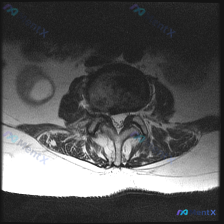

刚整理了一份腰椎MRI读片病例,只有单张轴位T2加权图像,把完整的分析思路整理出来和大家分享。 一、影像基本信息 这是一张腰椎MRI轴位T2加权图像,清晰度良好,解剖结构辨识度高: - 扫描水平为腰椎单个节段(大概率L4/5或L5/S1,具体需结合矢状位确认) - T2序列特征符合典型表现:脑脊液高...

收到一份腰椎MRI T2轴位单层影像,问题是评估椎间盘病变,我整理了完整分析思路和大家分享。 一、基本影像信息 这是腰椎层面的轴位T2序列图像,先给大家整理观察到的客观表现: 1. 骨性结构:椎体骨髓信号均匀,双侧关节突关节形态对称,间隙清晰,没有明显骨赘、硬化,椎体后缘也没有骨质增生 2. 椎间盘...